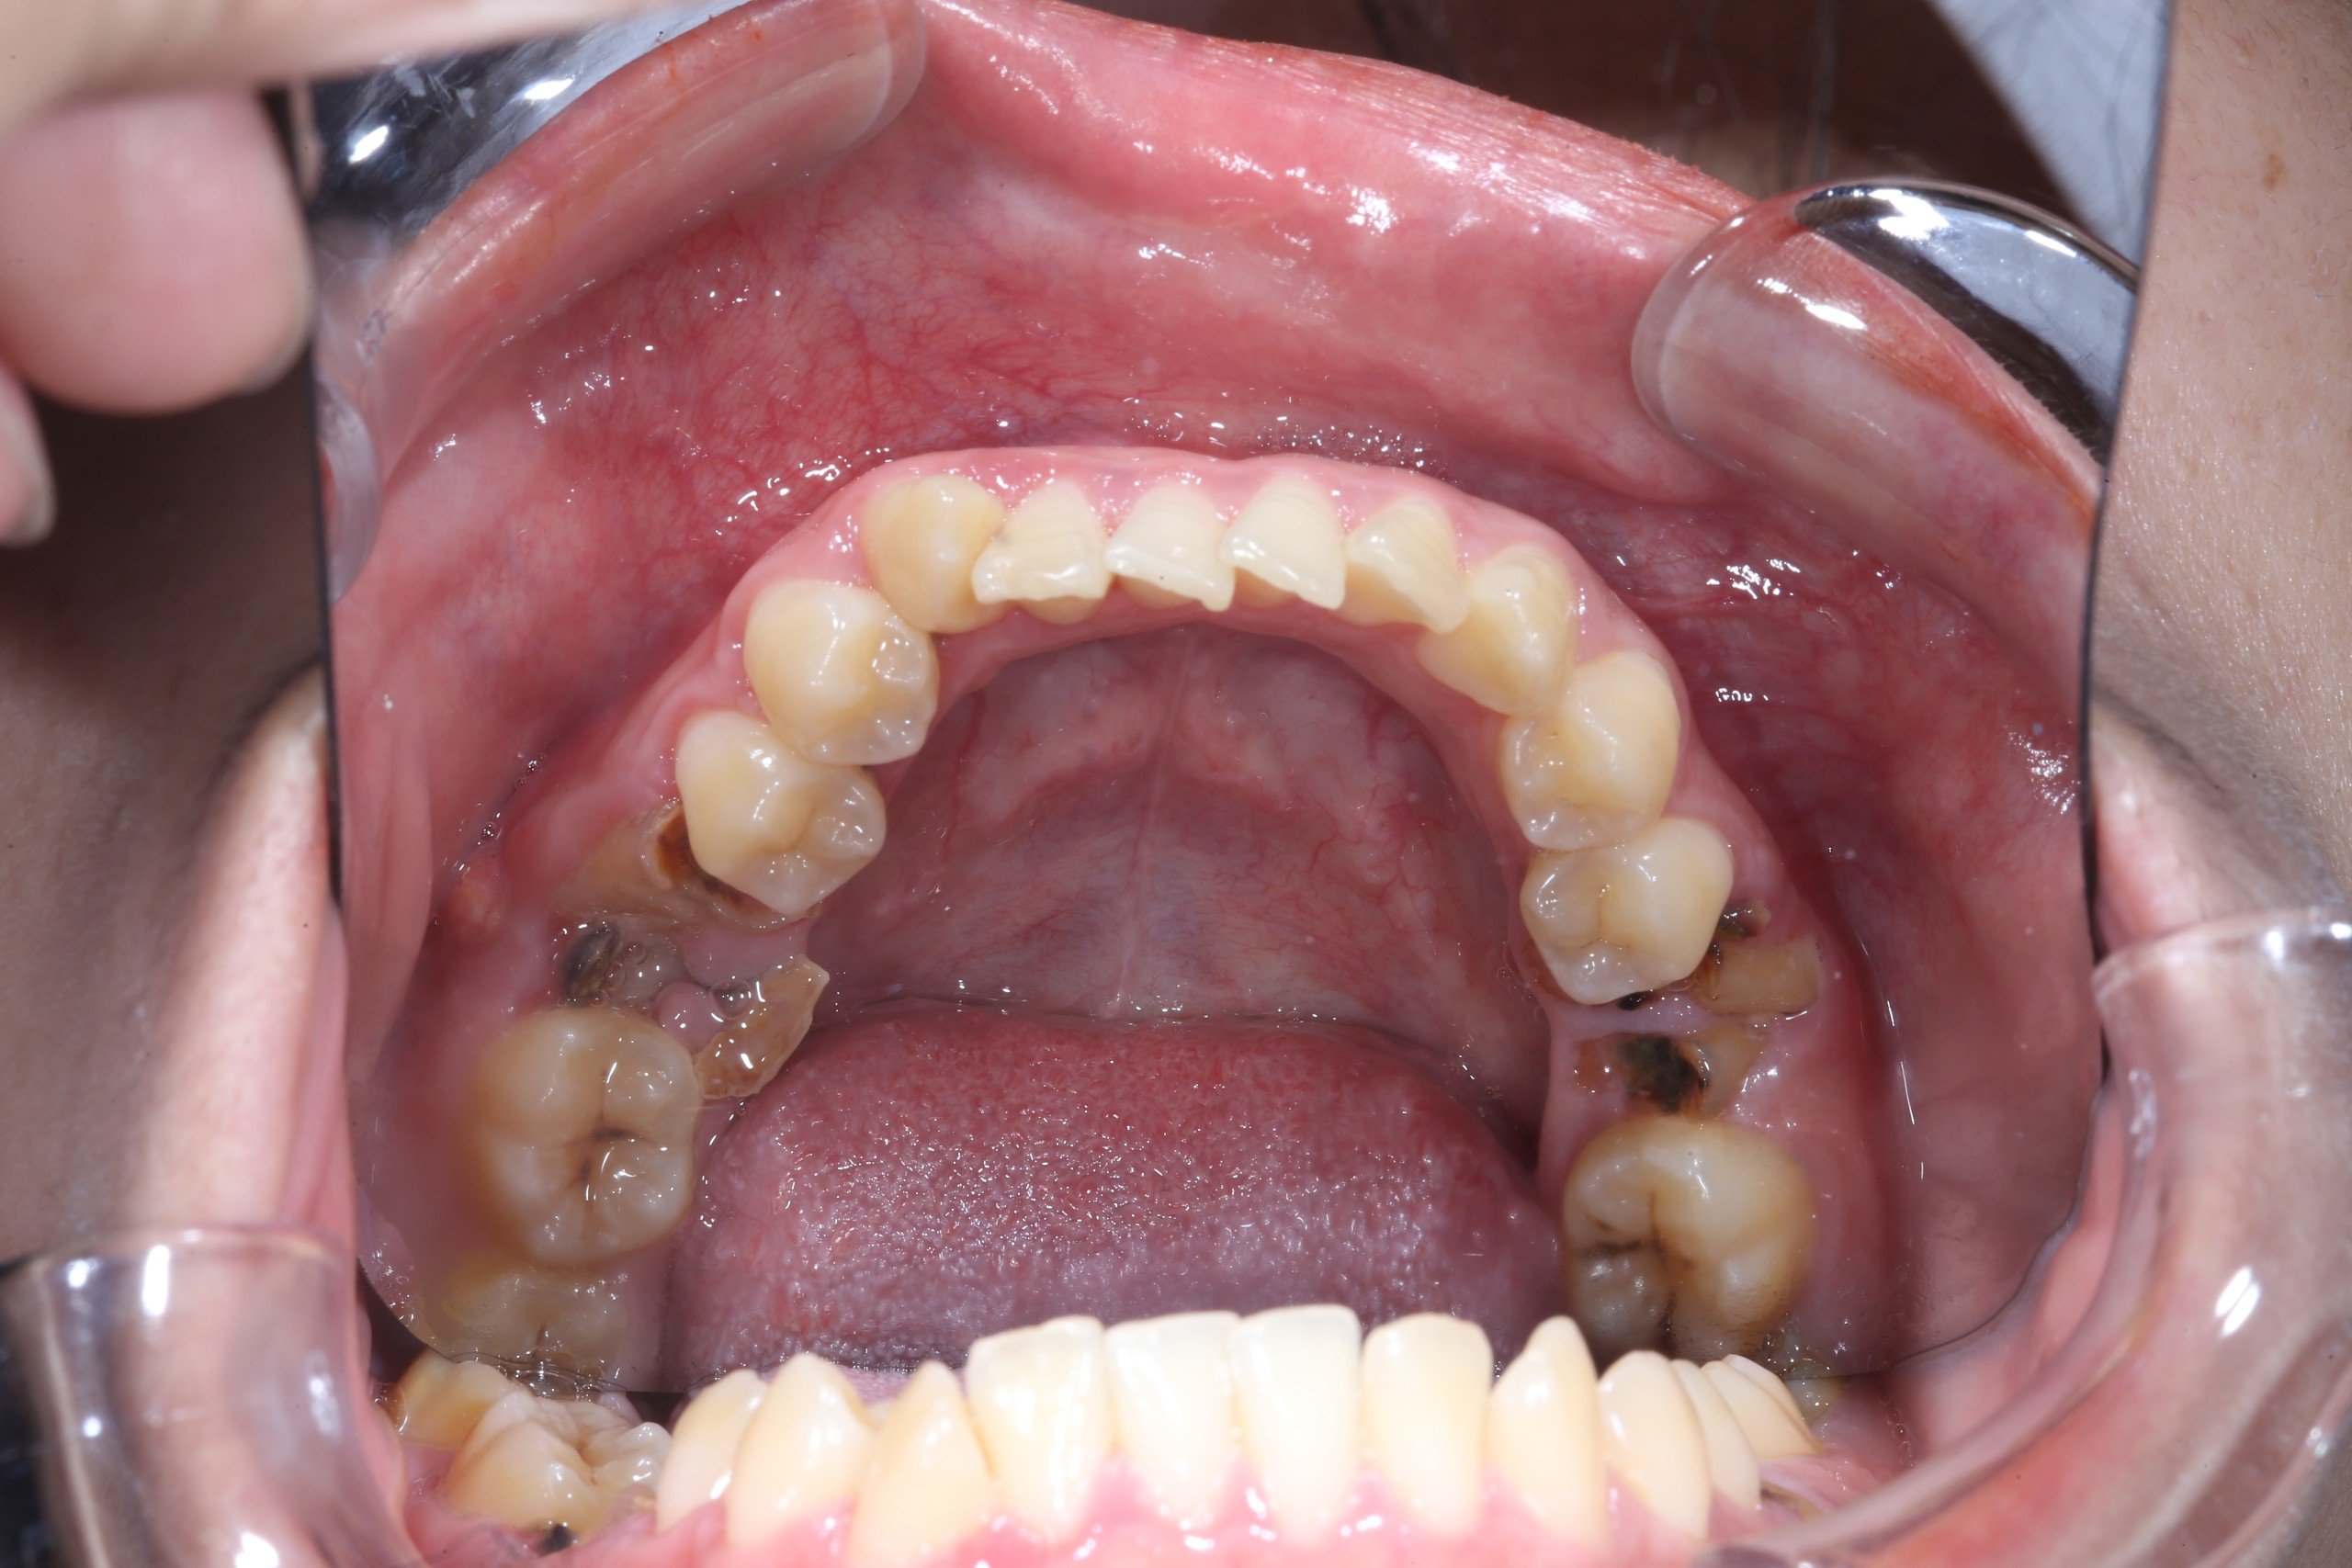

Trên cung hàm của người trưởng thành thường có 32 chiếc răng vĩnh viễn, bao gồm cả răng khôn. Răng hàm số 6 thường được biết đến với tên gọi khác là răng cối, và chúng có vai trò quan trọng trong quá trình nhai và nghiền thức ăn. Đặc điểm của răng số 6 bao gồm:

- Vị trí của răng này nằm sâu bên trong hơn so với các răng khác, điều này làm cho việc vệ sinh răng thứ 6 trở nên khó khăn hơn.

- Sâu răng: Khi răng hàm số 6 bị sâu trong thời gian dài và không được điều trị kịp thời, men răng, ngà răng và thân răng có thể bị ăn mòn, dẫn đến tình trạng mất răng.

- Viêm quanh răng: Tình trạng này có thể xuất phát từ viêm lợi, việc vệ sinh răng miệng không đúng cách, không thường xuyên lấy cao răng, hoặc do các yếu tố như hút thuốc lá, uống rượu, hoặc mắc bệnh tiểu đường. Nếu không được điều trị, viêm quanh răng có thể lan rộng và gây tổn thương nghiêm trọng cho cấu trúc xương quanh răng, dẫn đến tình trạng mất răng.